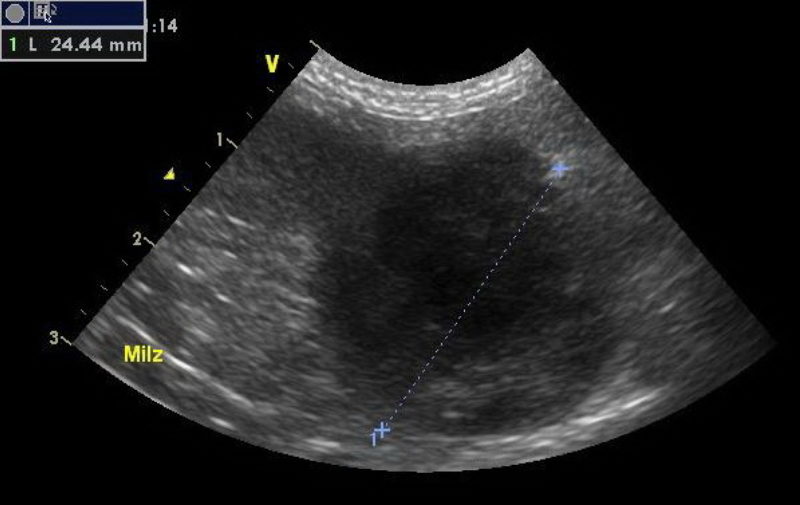

Um die Ursache zu ergründen, wurde bei Lisa eine Ultraschalluntersuchung des Bauchraumes durchgeführt. Hierzu wird der Patient mit dem Rücken in eine weiche kuhlenförmige Matte gelegt, der Bauch geschoren, mit Ultraschallgel bestrichen und mit verschiedenen Sonden „abgefahren“. Leider sind die Veränderungen, die wir im Bauchraum von Lisa finden, gar nicht schön: so ist in der Milz ein Tumor, der alsbald die Größe einer Faust hat. Darüber hinaus ist die gesamte Leber von Tumoren durchsetzt, und so kommt eine eventuelle chirurgische Hilfe für die kleine Hündin leider zu spät.

Ohne Milz, die relativ problemlos operativ entfernt werden kann, kann ein Organismus unproblematisch leben, ohne Leber leider nicht. Auch wenn die Tumore in Milz und Leber noch nicht aufgebrochen sind - was jedoch jederzeit passieren kann - und in die Bauchhöhle bluten, können wir Lisa nur noch palliativ behandeln. Im Vordergrund steht dann der bestmögliche Erhalt der Lebensqualität des Tieres und die Linderung von Schmerzen und anderer Symptome.